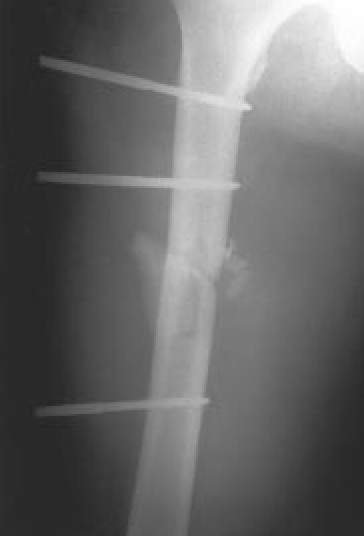

| Fig. 7A.: Fractura abierta de fémur, que clínicamente presentaba ausencia de pulsos distales a la lesión |

| Fig. 7C.: Control de reducción postoperatoria, tras osteosíntesis con fijador externo AO y reparación vascular |